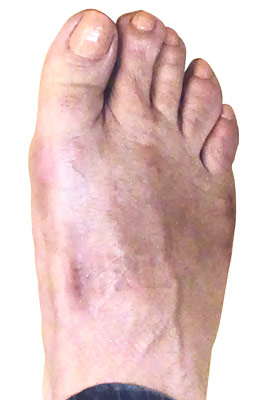

Before

Lapidus Forever Bunionectomy™ and Hamertoe Correction before

After

Lapidus Forever Bunionectomy™ and Hamertoe Correction after

Lapidus Forever Bunionectomy™ and Hamertoe Correction

Amanda is a 37-year-old mother who could not take much time off her foot and needed correction of a very large bunion (hallux valgus) that had also resulted in a hammertoe and partial discoloration of the 2nd toe joint. Amanda had a Lapidus Forever Bunionectomy™ and was back on her foot at 2 weeks after surgery and able to take care of her young children while she healed. Her bunion correction results are amazing, and her foot is fully back to normal.